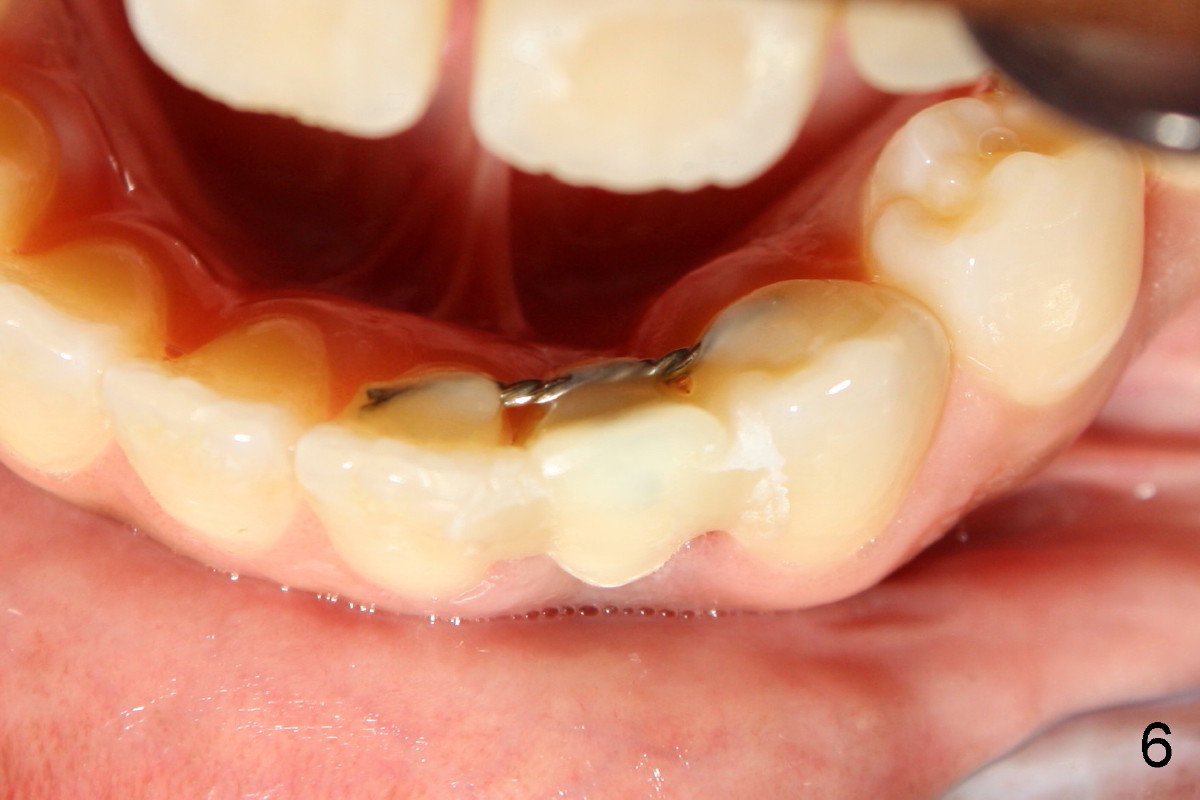

A 44-year-old black lady with ortho several years ago requests fixed restoration for #23 with narrow mesiodistal width (Fig.1). Treatment options are proposed: fixed prosthetic denture and implant. After discussion of advantages and disadvantages of each option, the patient agrees to have implant restoration. A 1.5 mm pilot drill is used to create osteotomy (Fig.2,3). After using 2.0 mm and 3.0 mm tapered osteotomes through the cortex at the crest, 3x17 mm 1-piece implant is placed (Fig.4) and temporary crown is immediately cemented with no centric or lateral occlusion. The patient is doing fine postop, although there is very mild percussion involving the tooth #24, three days postop. Fig.5 and 6 show that the temporary crown is bonded to the neighboring teeth interproximally and lingually. Retrospectively, ortho should have been done to torque the root of the tooth #22 prior to implant placement. Fig.3,4 show that there is space between #21 and 22.